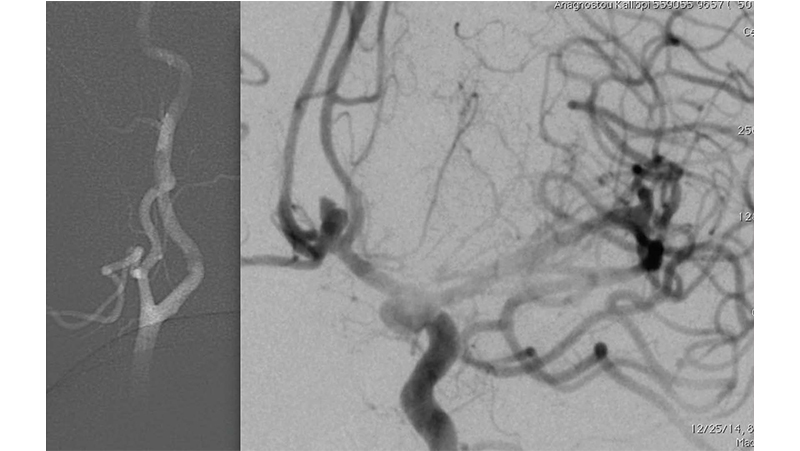

Εικόνα 1: Αγγειογραφία της αριστερής έσω καρωτίδος: Ραγέν ανεύρυσμα της προσθίας αναστομωτικής αρτηρίας.

Εικόνα 2: Έγινε εμβολισμός του ανευρύσματος στην οξεία φάση με coils. Στην τελική αγγειογραφία, φαίνεται η πλήρης απόφραξη του ανευρυσματικού σάκκου. Διακρίνουμε όμως και την απόφραξη του Μ1 της αριστεής μέσης εγκεφαλικής αρτηρίας, από θρόμβο που πιθανότατα αποσπάστηκε από την αυχενική έσω καρωτίδα κατά τους χειρισμούς (σημειωτέον ότι η επέμβαση έγινε χωρίς ηπαρίνη επειδή το ανεύρυσμα ήταν ραγέν.